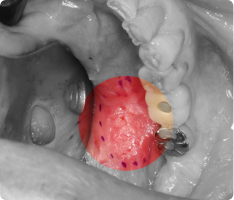

영구치가 나와야 할 시기가 지났는데 잇몸 속에 묻혀 나오지 못하는 치아가 있습니다.

이를 ‘매복치’라고 하며, 흔히 송곳니(견치)에서 많이 발생합니다.

치아가 스스로 나오지 못하면, 교정치료와 함께 개창술을 통해 치아를 밖으로 끌어내야 합니다.

- 국소마취 후, 치아가 묻혀 있는 잇몸을 작게 열어 치아 머리(치관)를 노출시킵니다.

- 치아 표면에 교정용 버튼(장치)을 부착하고, 교정력(작은 고무줄·와이어)을 이용해 치아를 이동시킵니다.

- 수술 자체는 짧고 안전하게 진행되며, 이후에는 교정치료와 병행하여 서서히 치아가 배열됩니다.